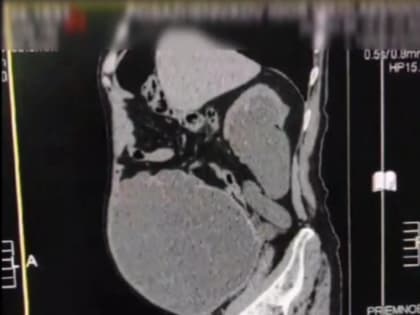

Врачи вывели 9 литров мочи из пациента в Ижевске

Специалисты оказали помощь пациенту с дивертикулом мочевого пузыря Григорий Кудреватых Переполненный мочевой пузырь.

Ижевские врачи вывели из мочевого пузыря пациента 9 литров мочи

У пациента сформировался дивертикул мочевого пузыря. Ижевск, Удмуртия.